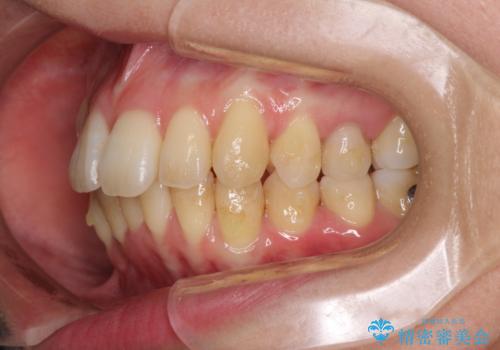

突出した印象のあった前歯をきれいに引っ込めることができたので、口が閉じやすくなり、横顔の印象をスッキリとさせることができました。

でこぼこしていて磨きにくかった歯と歯の間も清掃しやすくなり、患者様には大変満足していただきました。